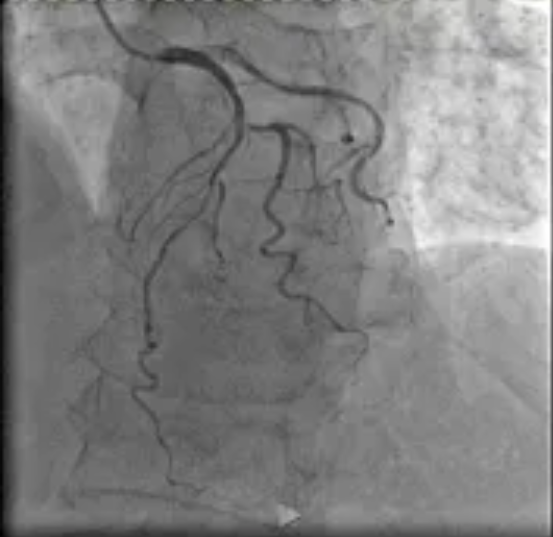

日前,91porn阳逻院区心血管内科收治一名冠状动脉疾病患者,CT检查显示冠状动脉左前降支存在病变,最严重处狭窄达85%且伴有钙化。

在91porn 心血管内科主任李昌教授的指导下,阳逻院区心内团队运用冠状动脉血管内超声(IVUS)技术详细检查患者血管,发现主支血管狭窄程度处于临界状态,可暂时通过药物治疗来优化;分支血管严重狭窄,需要进行介入治疗。基于IVUS提供的精准信息,患者避免了不必要的支架植入,有效降低手术风险。这一精准化治疗方案,既减少患者创伤与经济负担,又降低术后并发症风险,为患者的健康提供了有力保障。

患者IVUS检查影像报告